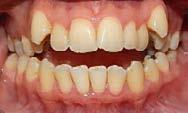

Se presenta una paciente de 29 años con el motivo de consulta “quiero arreglarme los dientes” en los

estudios de inicio se observa en la radiografía lateral de cráneo (Figura 1) clase II esquelética y crecimiento vertical. En los estudios de inicio extraorales en las fotografías de frente y perfil (Figura 2) no muestra exposición dental al momento de sonreír, un perfil convexo y el tercio inferior aumentado respecto al tercio superior y medio de la cara.

Estudios intraorales iniciales

En las fotografías intraorales (Figura 3) observamos una clase II molar bilateral, clase II canina derecha, clase III canina izquierda, apiñamiento severo superior y moderado inferior, presencia de mordida abierta anterior y posterior a nivel de premolares (Figura 4), forma de arco triangular en la arcada superior y forma de arco oval en inferior, ausencia del OD 46 y presencia de un diente supernumerario.